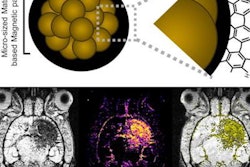

In a mouse model study of MRI-guided focused ultrasound-induced blood-brain barrier (BBB) opening at MRI field strengths ranging from approximately 0 tesla (outside the magnetic field) to 4.7 tesla, the static magnetic field dampened the detected microbubble cavitation signal and decreased the BBB opening volume. Image courtesy of Washington University in St. Louis.In the study, which included 30 mice, Chen's group discovered that the magnetic field of the MRI scanner reduced the blood-brain barrier's opening volume by 3.3-fold to 11.7-fold, depending on its strength.

"Static magnetic fields dampened microbubble cavitation activity and decreased trans-blood-brain barrier delivery by focused ultrasound combined with microbubble-induced blood-brain barrier opening," the researchers concluded.